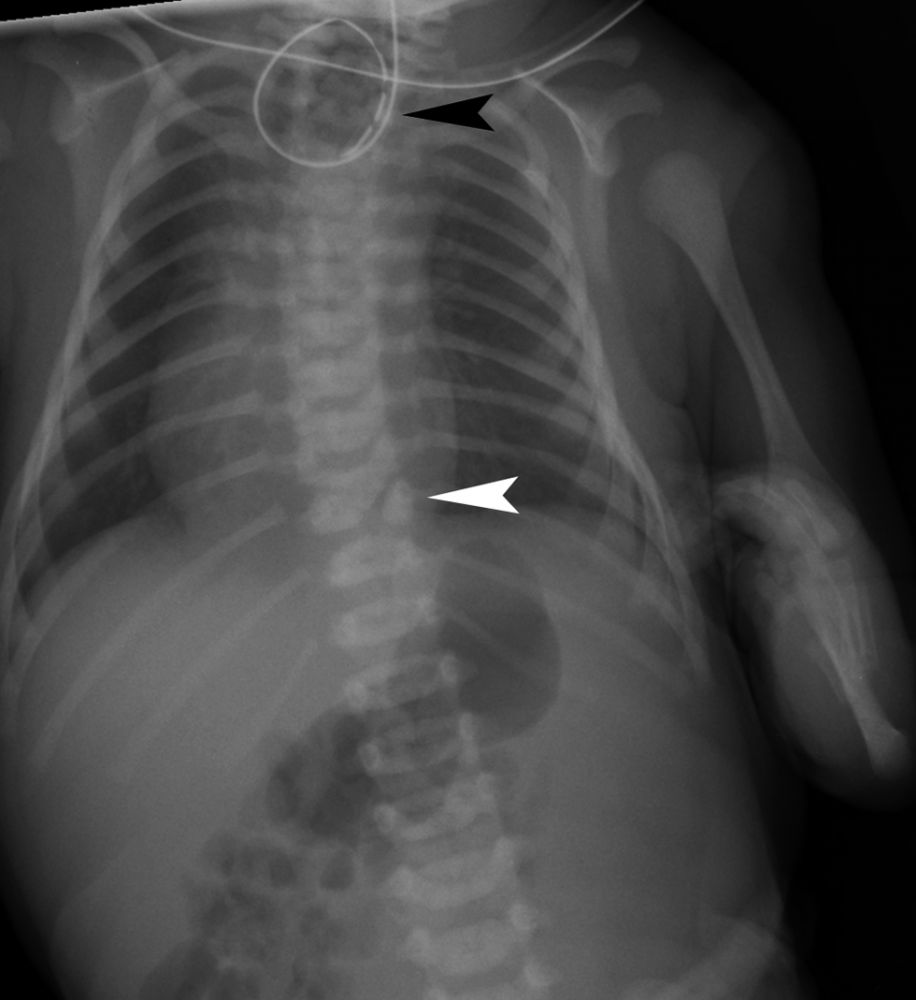

这是一个刚满月的宝宝,摆在医生面前的就这三样东西:一张胸部X光片、一张足部外观照、还有一张血常规化验单。

症状很明显但很分散,就像几个不相干的毛病,这就很考验模型捕捉碎片信息和综合分析的能力。

但WiseDiag V2并没有盲人摸象,而是整体思考:

在胸部X光片,锁定了食管闭锁和半椎体发育异常;

在足部外观照中精准识别了足部的马蹄内翻;

通过化验单的数值和胸部X光片读出了吸入性肺炎的风险。

综合所有信息给出正确的诊断结果——VACTERL联合征。

VACTERL联合征是一种罕见的非随机先天性多系统发育畸形组合,通常由至少三种特定器官缺陷组成:脊柱畸形(V)、肛门闭锁(A)、心脏缺陷(C)、气管食管瘘/食管闭锁(TE)、肾脏畸形(R)和肢体异常(L)

由此可见,WiseDiag V2是一个医疗AI强大的多模态认知底座。